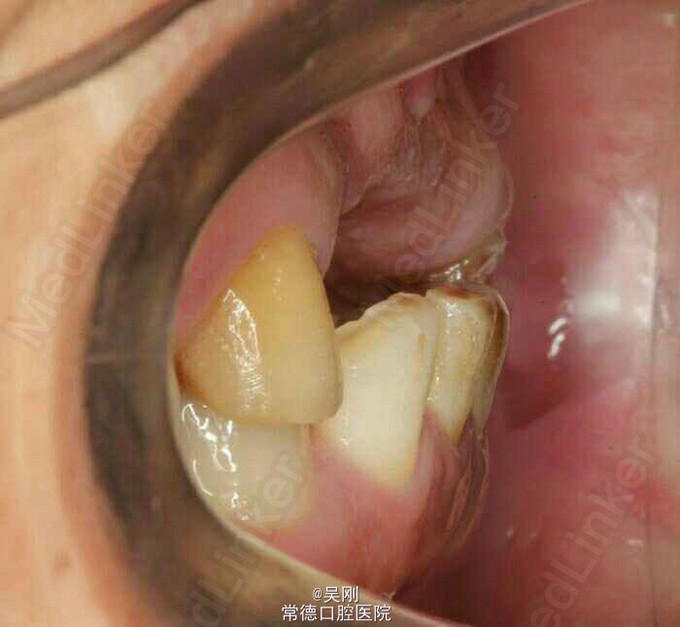

11、12、21缺失,牙槽骨(唇侧更明显)吸收严重成月牙状。 22残根断面距龈上约1.5mm,13牙髓坏死。 深覆 牙合 。 下前牙之间有间隙。 缺牙区距离太长,超过实际距离。 X线显示下前牙与上颌缺牙区牙槽嵴角度成反 牙合 。

上颌牙列缺损。 1.戴 牙合 垫,暂时恢复美观并为粘固下颌托槽开辟间隙。为防止 牙合 垫压低后牙而影响定位咬合关系,牙合 垫在前磨牙处不接触,距离抬高到能粘固托槽就好,尽量缩短佩戴时间。 2.将托槽按同一平面粘固,前牙减径约1mm(加上本身的间隙共产生约2.5mm),直接用圆丝(硬丝)挂一类牵引,使前牙牙轴具有舌向关闭间隙。 3.基牙预备,因缺牙区跨度超过实际长度选择增加14做基牙。 4.完成烤瓷桥。 5.X线显示磨牙还是有点牙低,下前牙明显内收,于上颌牙槽嵴关系改善。 6.因磨牙压低,下前牙舌侧固定保持。磨牙自己建 牙合 。